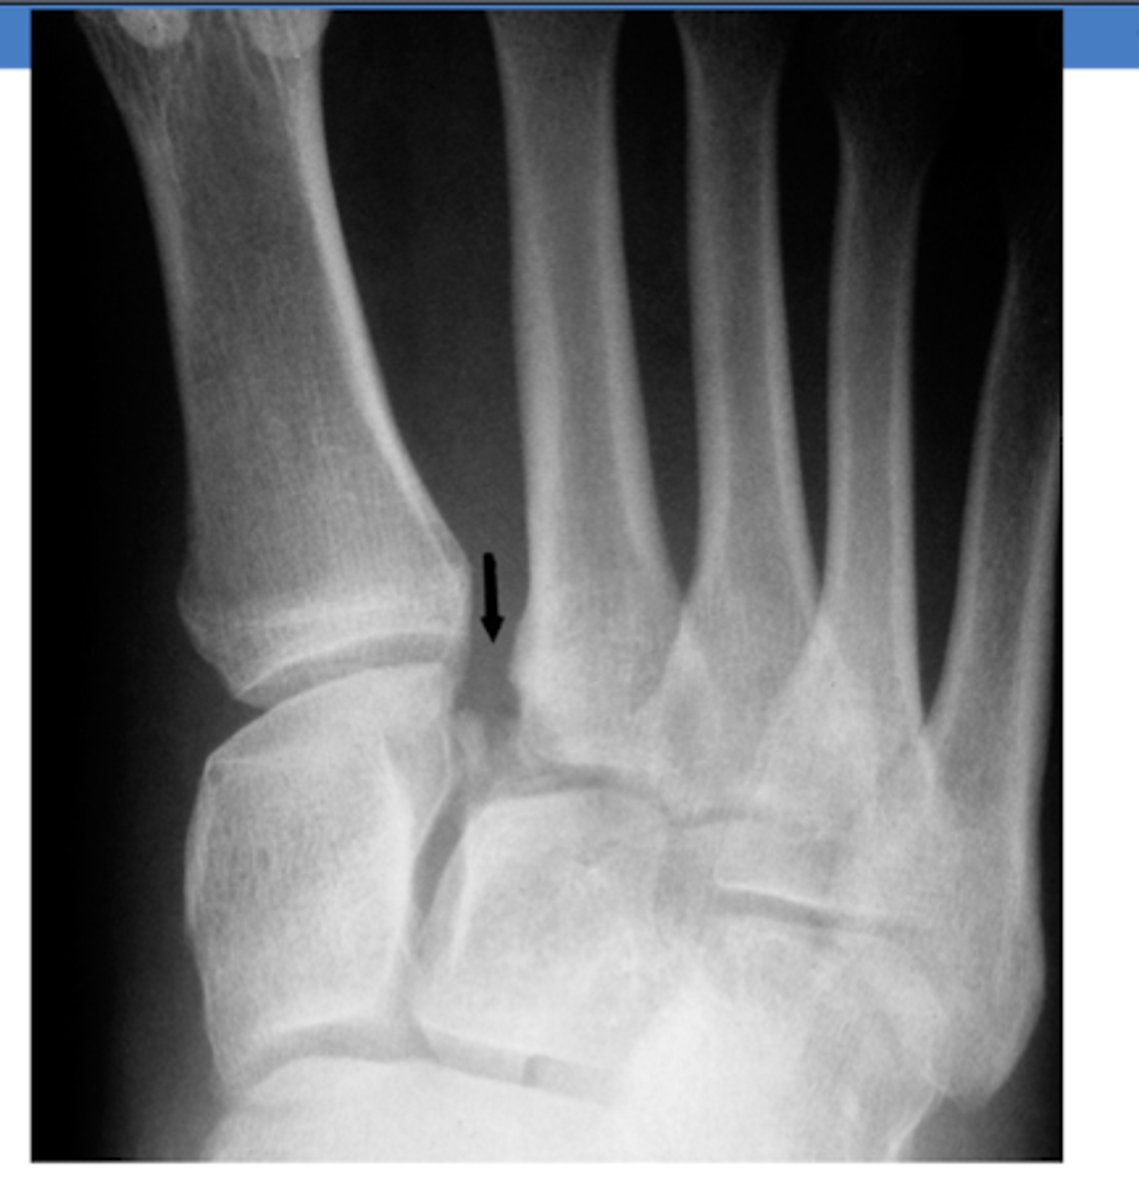

What TWO movements can lead to a Maisonneuve fracture?

pronation

external rotation

What TWO fractures occur together in a Maisonneuve fracture?

Fx of medial malleolus

Spiral fracture of the fibula

What TWO XR findings are consistent with a Maisonneuve fracture?

Tear of the tibiofibular ligament

Widening of the ankle mortise medially